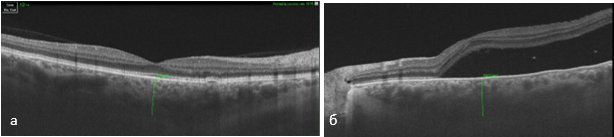

По данным ОКТ на правом глазу плоские отслойки пигментного эпителия вне фовеа, дистрофические очажки пигментного эпителия, пахисосуды хориоидеи, толщина хориоидеи 522 мкм, на левом глазу очень высокая отслойка нейроэпителия – 530 мкм, по верхневисочной сосудистой аркаде участки отслоения пигментного эпителия, интраретинальные включения средней рефлективности в проекции наружных слоев сетчатки, пахихориоидея, пахисосуды, зона с фокальной экскавацией хориоидеи. Толщина хориоидеи 587 мкм (рис.2, а, б; 3).

Рис.2. Пахисосуды хориоидеи: а) толщина хориоидеи 522мкм на правом глазу; б) толщина хориоидеи 587мкм на левом глазу.

Примечание: составлен авторами по результатам данного исследования